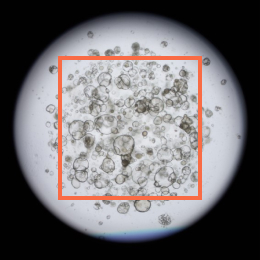

Step into the future of oncology with Lambda AF Solution’s Human Pancreatic Cancer Organoids. Crafted with cutting-edge 3D culture technology, these organoids bring the complex environment of pancreatic cancer right to your lab. Perfect for delving into tumor heterogeneity and enhancing drug testing—pioneering precision medicine starts here!

Pancreatic cancer organoid

Cancer organoid | ![]() | ![]() | ![]() | ![]() |